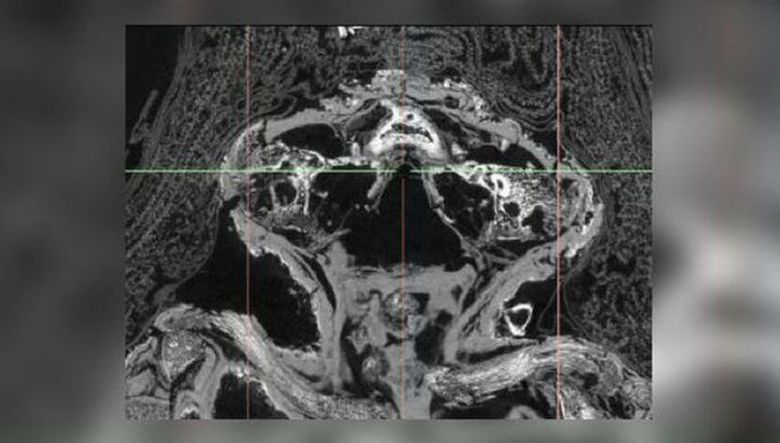

És nemrégiben alaposan elvégezték a “sólya múmiáját” szkennelés (a mikro-CT szkennelés lehetővé teszi a tudósok számára, hogy láthassák, és azt jelenti, és gondosan tanulmányozza a múmia belső tartalmát anélkül, hogy eltávolítaná és a temetkezési anyag megsértése nélkül) más múzeummal együtt kiállítást. Mi volt a meglepetés a kutatók számára, amikor ők voltak rájött, hogy ezek a maradványok nem a madárhoz tartoznak, de halva született koraszülött.

Kiderült, hogy ez a gyermek még mindig méhben szenved olyan ritka betegség, mint anencephaly, amelyben nem alakulnak ki az agy és maga a koponya, ami vetélést okozott. A gyermek körülbelül 25 hete volt, már kialakult test, végtagok, akár a lábujjak és a karok, de a koponya felső része – nem. Ezen felül szenvedett veleszületett ajkak hasadékán is hívják a szájpadra. Egy másik dolog meglepő: miért van ez? vetélés mumifikálódott? Általában az ilyen “gyerekek” az ókori Egyiptomban (és nem csak benne), csak edényekbe temetve, és csak az a legritkább esetek pontosan úgy történt, ahogy látjuk – mumifikálódott. Úgy tűnik, hogy a gyermeket különlegesnek, és az őt is halott születés – méltó indulás a halottak világába …